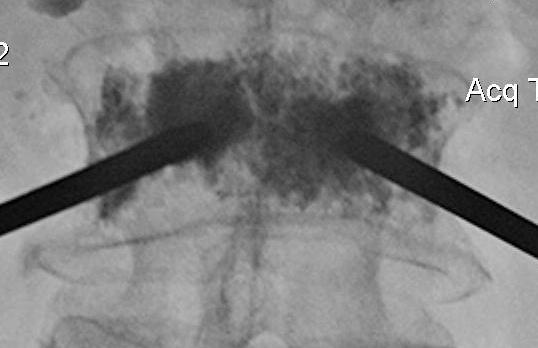

Technique

Percutaneous

- trochar into pedicle under fluoroscopy

- injection PMMA

- then inject PMMA